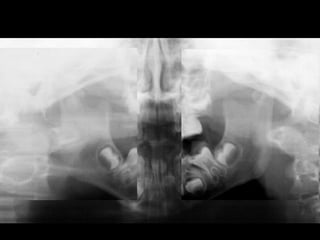

Panoramic (reconstructed from CT)

When looking to the condyle from an anterior view, one can see the oblong

shape of a condyle but the left condyle is smaller.

!

The midline are not coincident. Note that the lower midline is toward right like

the occlusal plane canting to the right. This can be explained by the lack of

heigh of the left ramus and as normal growth occur, there is a wagon wheel

effect and the midline deviate toward the normal side, the occlusal plane is

moving up on the affected side.